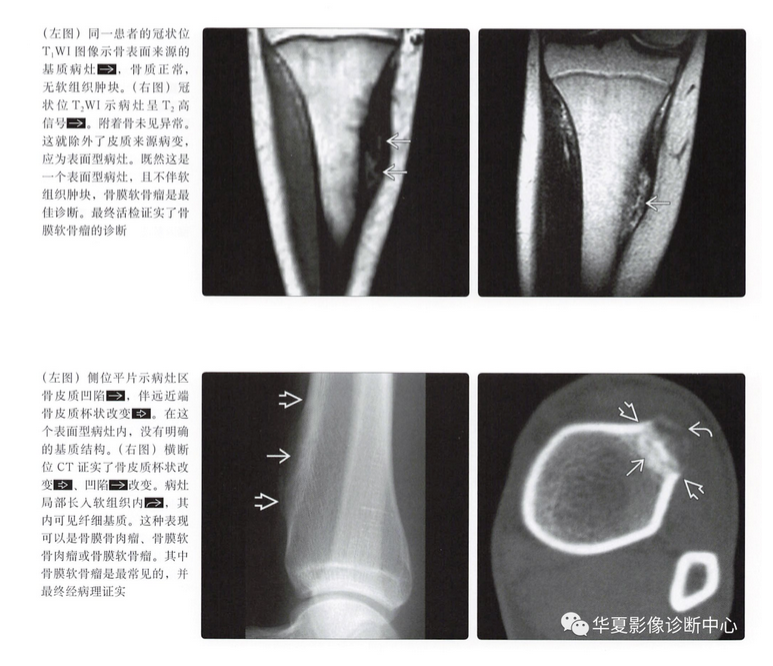

MR表现

- 病灶的结节状形态

- T1上等或低信号

- T2上高信号

- 不均匀强化,通常呈边缘强化

- 髓内累及(20%)

- 不规则软组织肿块(30%)

骨膜软骨肉瘤

- 几乎与骨膜软骨瘤影像表现相同

- 类似的MR特征

- 低级别软骨形成小叶结构,液体敏感序列上呈高信号

- 边缘强化,伴比较小的软组织肿块

- 表面型病灶彼此之间常常难以鉴别

- 如果T2图像上可见高信号小叶,提示为骨膜软骨瘤

- 骨膜软骨肉瘤与骨膜软骨瘤影像上鉴别点很少